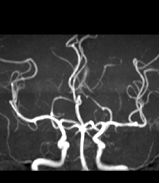

2.2 MR的發(fā)展

臨床要求病變得到多方位展示,更促進(jìn)多領(lǐng)域整合,例如:MR-US、MR-PET、MR-CT、MR-Surgery、MR-Molecule Imaging.高場(chǎng)磁共振出現(xiàn)。針對(duì)不同疾病,磁共振特異性造影劑的不斷出現(xiàn)。